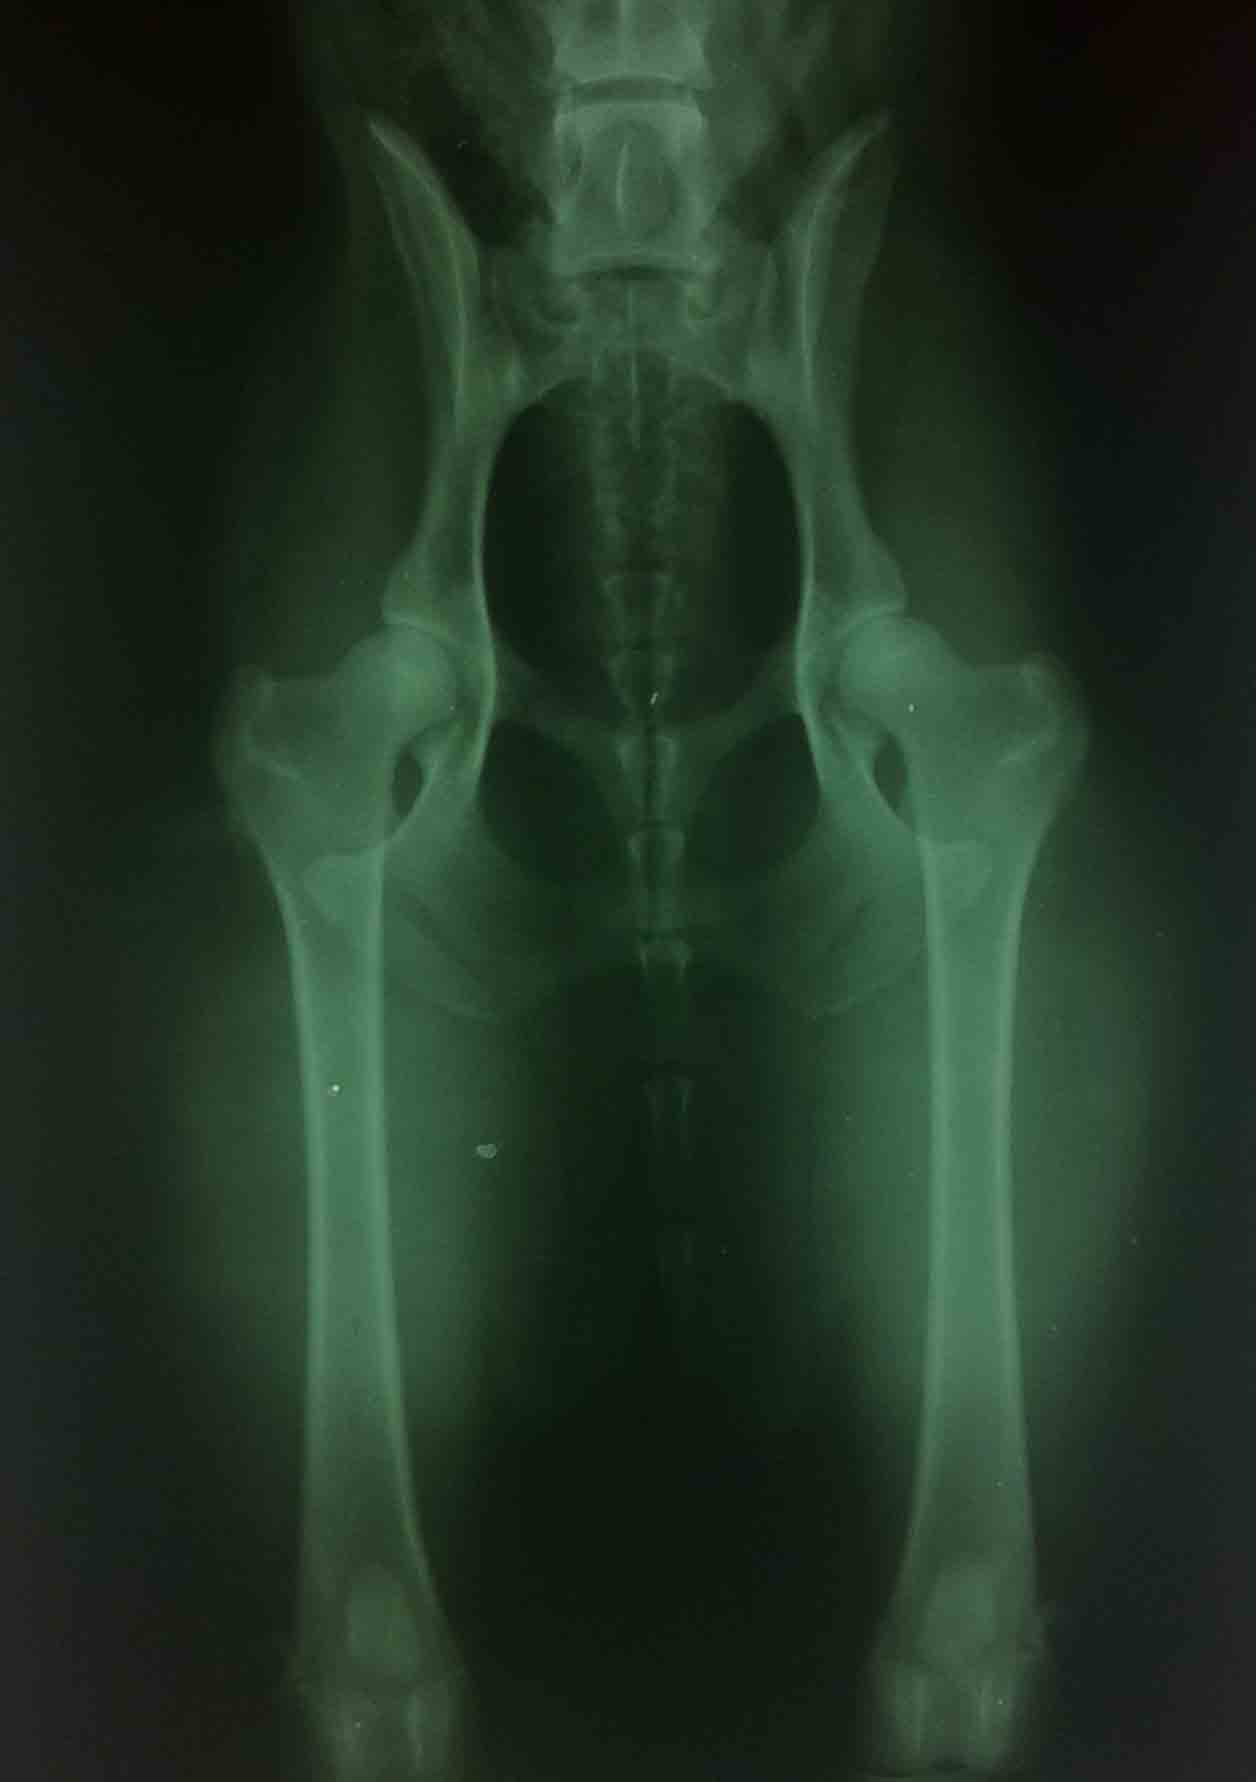

CARRA byla na vyšetření dysplazii kyčelních kloubů s krásným výsledkem

Bez příznaků DKK A